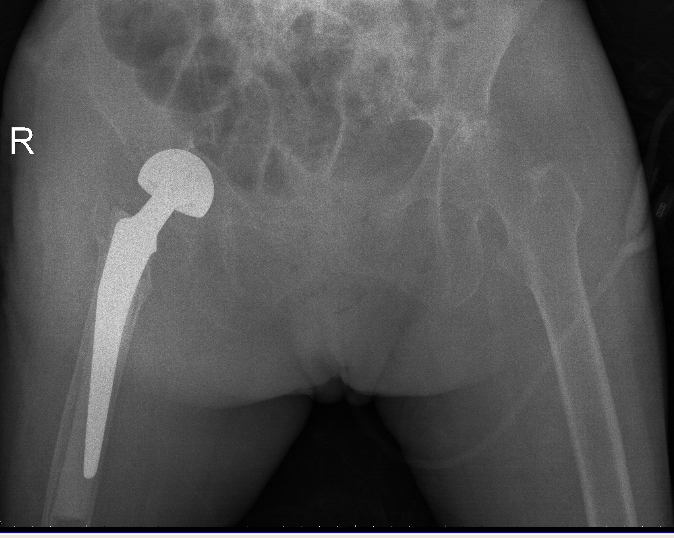

△骨科于15日、16日收治的另外兩位高齡患者

△術後